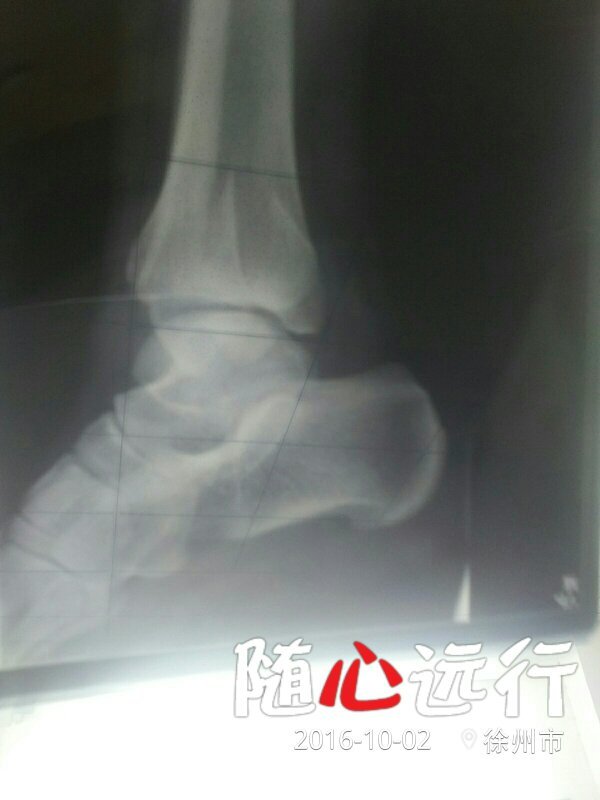

我现在怀孕三十二周了左脚踝骨折二十五天了,在过一个月能慢慢下地走路吗?求解 付上片子 点击展开 133*****340_heC3 2016-10-02 13:59 满意回答 从目前恢复的情况来搁悠告看,可以的,间金这段时荒葵间一定要注意休息,多补钙,营养均衡。 yuhaobbmc 2016-10-02 14:06 宝宝知道提示您:回答为网友贡献,仅供参考。 相关问题 左脚后跟粉碎性骨折做内固定手术八个月现在走路一 我小孩五岁左脚距骨骨折有点移位,医生说不管他,不用药物治疗,请问这样能完全灰复吗?要多久能走路 我的脚骨折九个月了,走路还很痛,拍片子骨头长好了,现在骨质疏松,该怎么办